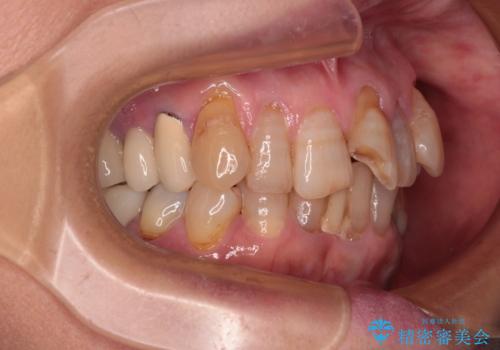

- 長年気にしていた捻れた前歯が欠けたとのことで来院された患者様です。

矯正治療に抵抗があったそうですが、前歯が欠けたことをきっかけに、矯正治療で歯列を整えた上で、セラミッククラウン治療を行う決心が付いたとのことでした。

デコボコが強いため、ブリッジや残根となっている部分のスペースを利用して歯列を整え、変色や欠けている歯をオールセラミッククラウンによる補綴治療を行うこととしました。